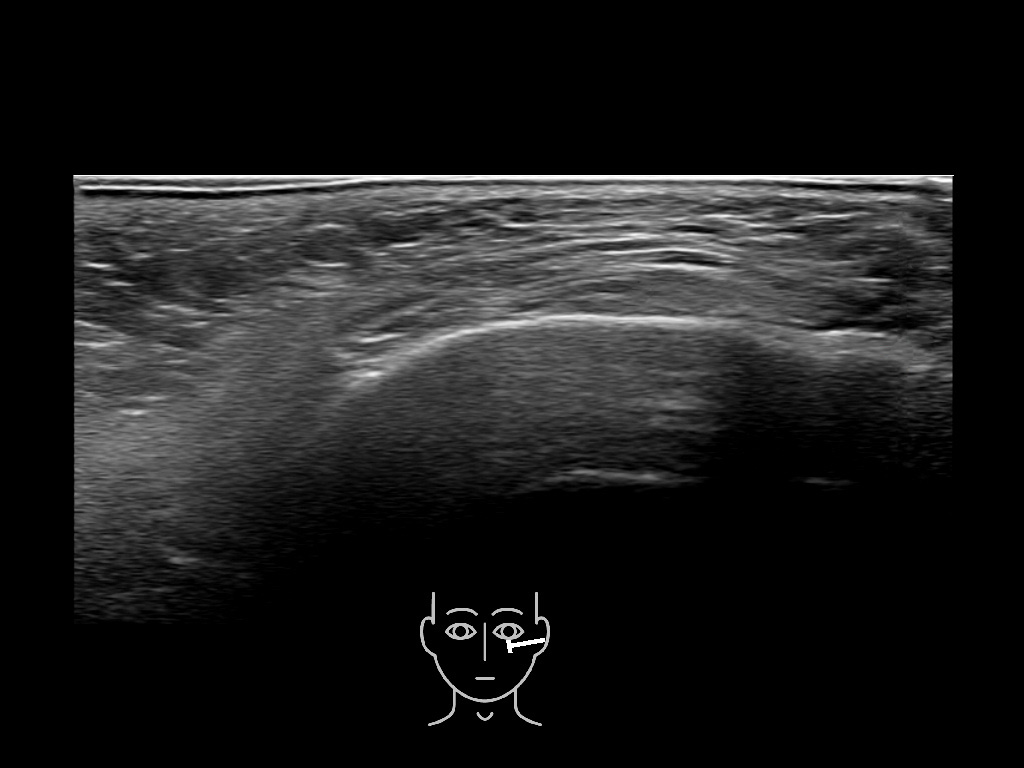

Draw in the image on the right where the fillers are located. To check if your answer is correct, please click on the secondary image.

Fillers